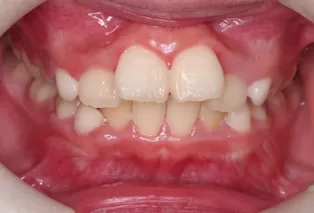

Photos intra-orales